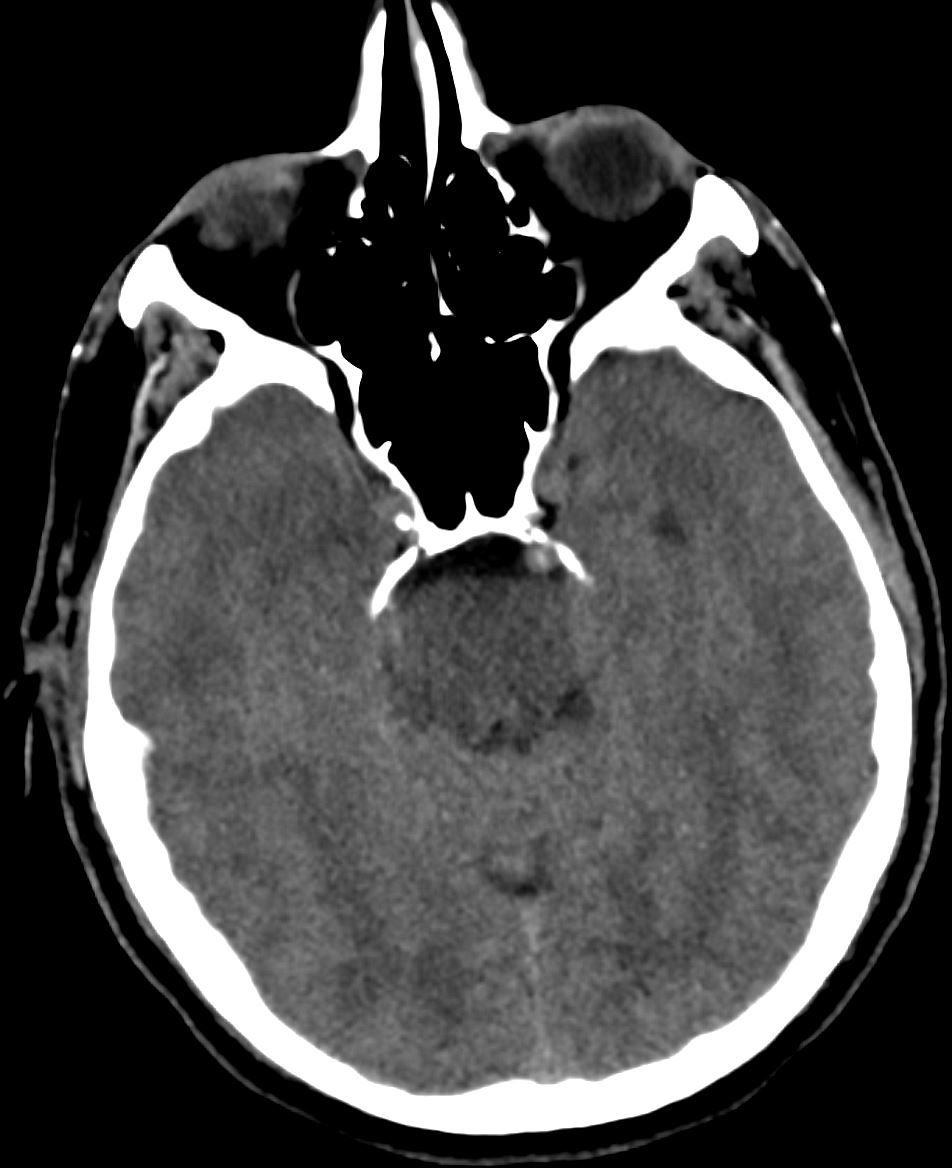

Image IQ Quiz: Middle-Aged Man Presents with Left-Sided Weakness

Middle age male with left sided weakness. What is the most likely diagnosis? What radiology sign is demonstrated?